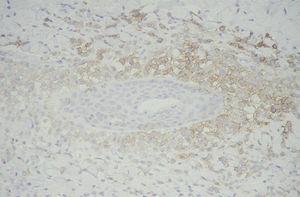

Las células de Langerhans son largas células ovoidales, de unos 12-15 mm de diámetro, de bordes mal definidos, con abundante citoplasma eosinófilo y un núcleo excéntrico en forma de «grano de café» (fig. 11). Como hemos adelantado, presentan marcadores inmunohistoquímicos característicos como S100, CD1a, CD45, HLA-DR, CD4, CD2 y T200 (fig. 12) 12. Comparten con el sistema monocito/macrofágico algunos antígenos comunes: CD1a, CD11 y CD45.

Fig. 12.--Inmunohistoquímica con CD1a, que tiñe selectivamente las células de Langerhans. (CD1a, x40.)

Existen algunos marcadores que diferencian a las células que se acumulan en esta enfermedad de las células de Langerhans de la piel normal que son la fosfatasa alcalina placentaria, la aglutinina del cacahuete, el receptor para el interferón-g y los marcadores CD11c, CDW32, CD68, CD14 22,31,59. Son negativas para Mac-387, que tiñe las células del sistema fagocítico mononuclear. Tampoco expresan CD34 ni MS-1, que son marcadores de células endoteliales sinusoidales y de macrófagos dendríticos perivasculares.